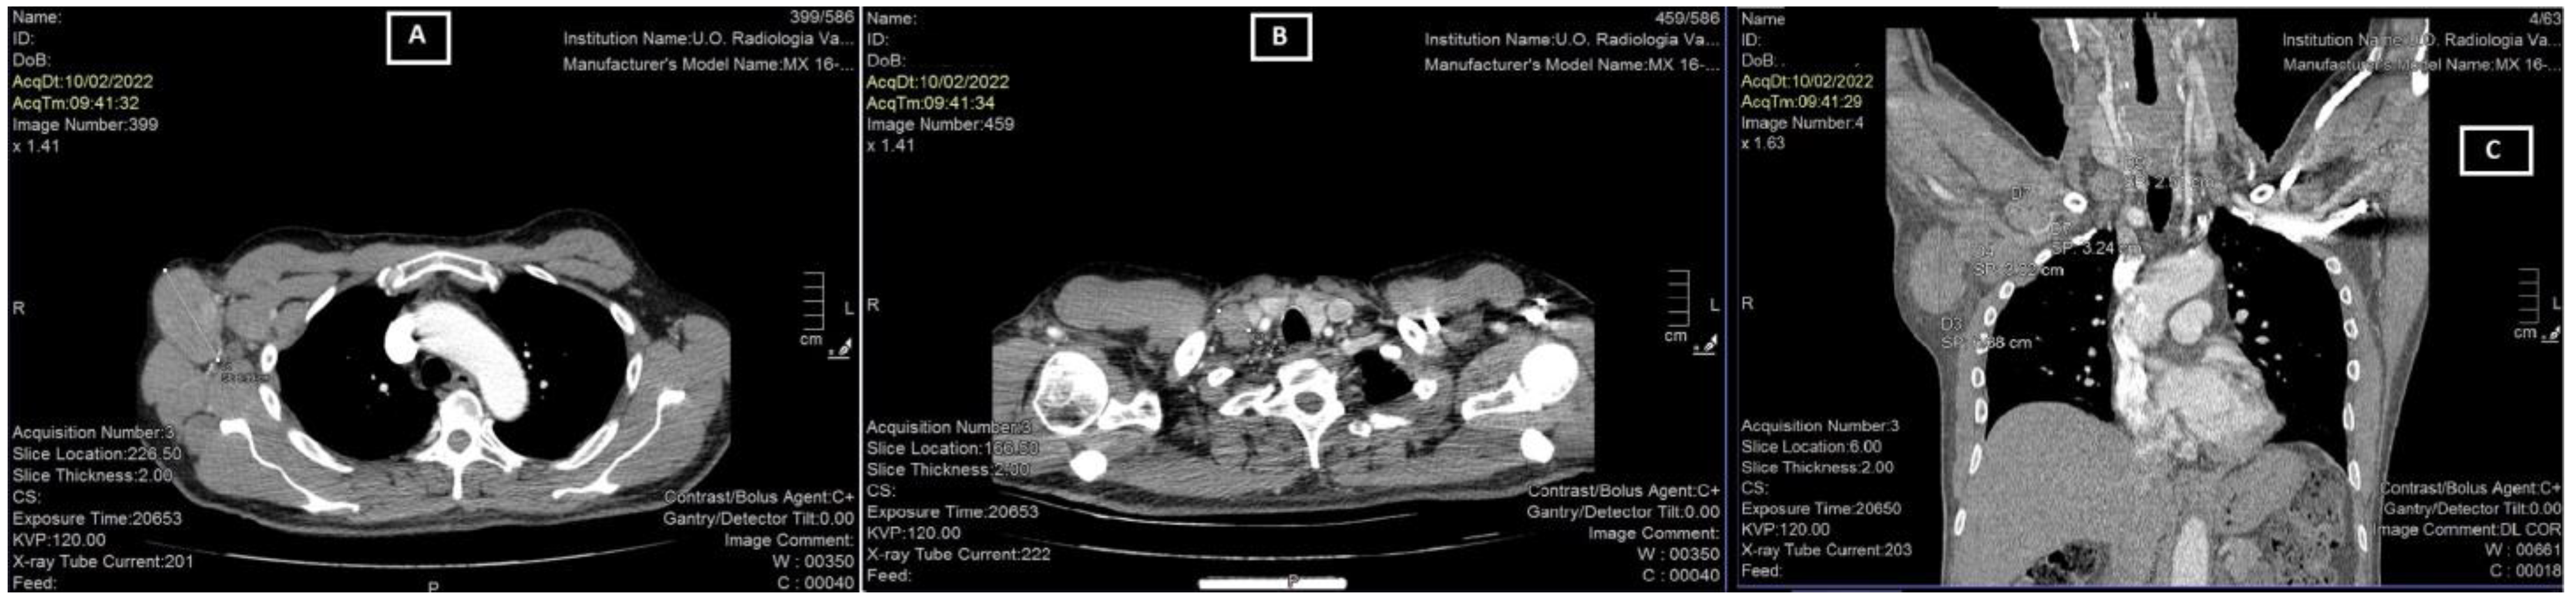

2. Case Report